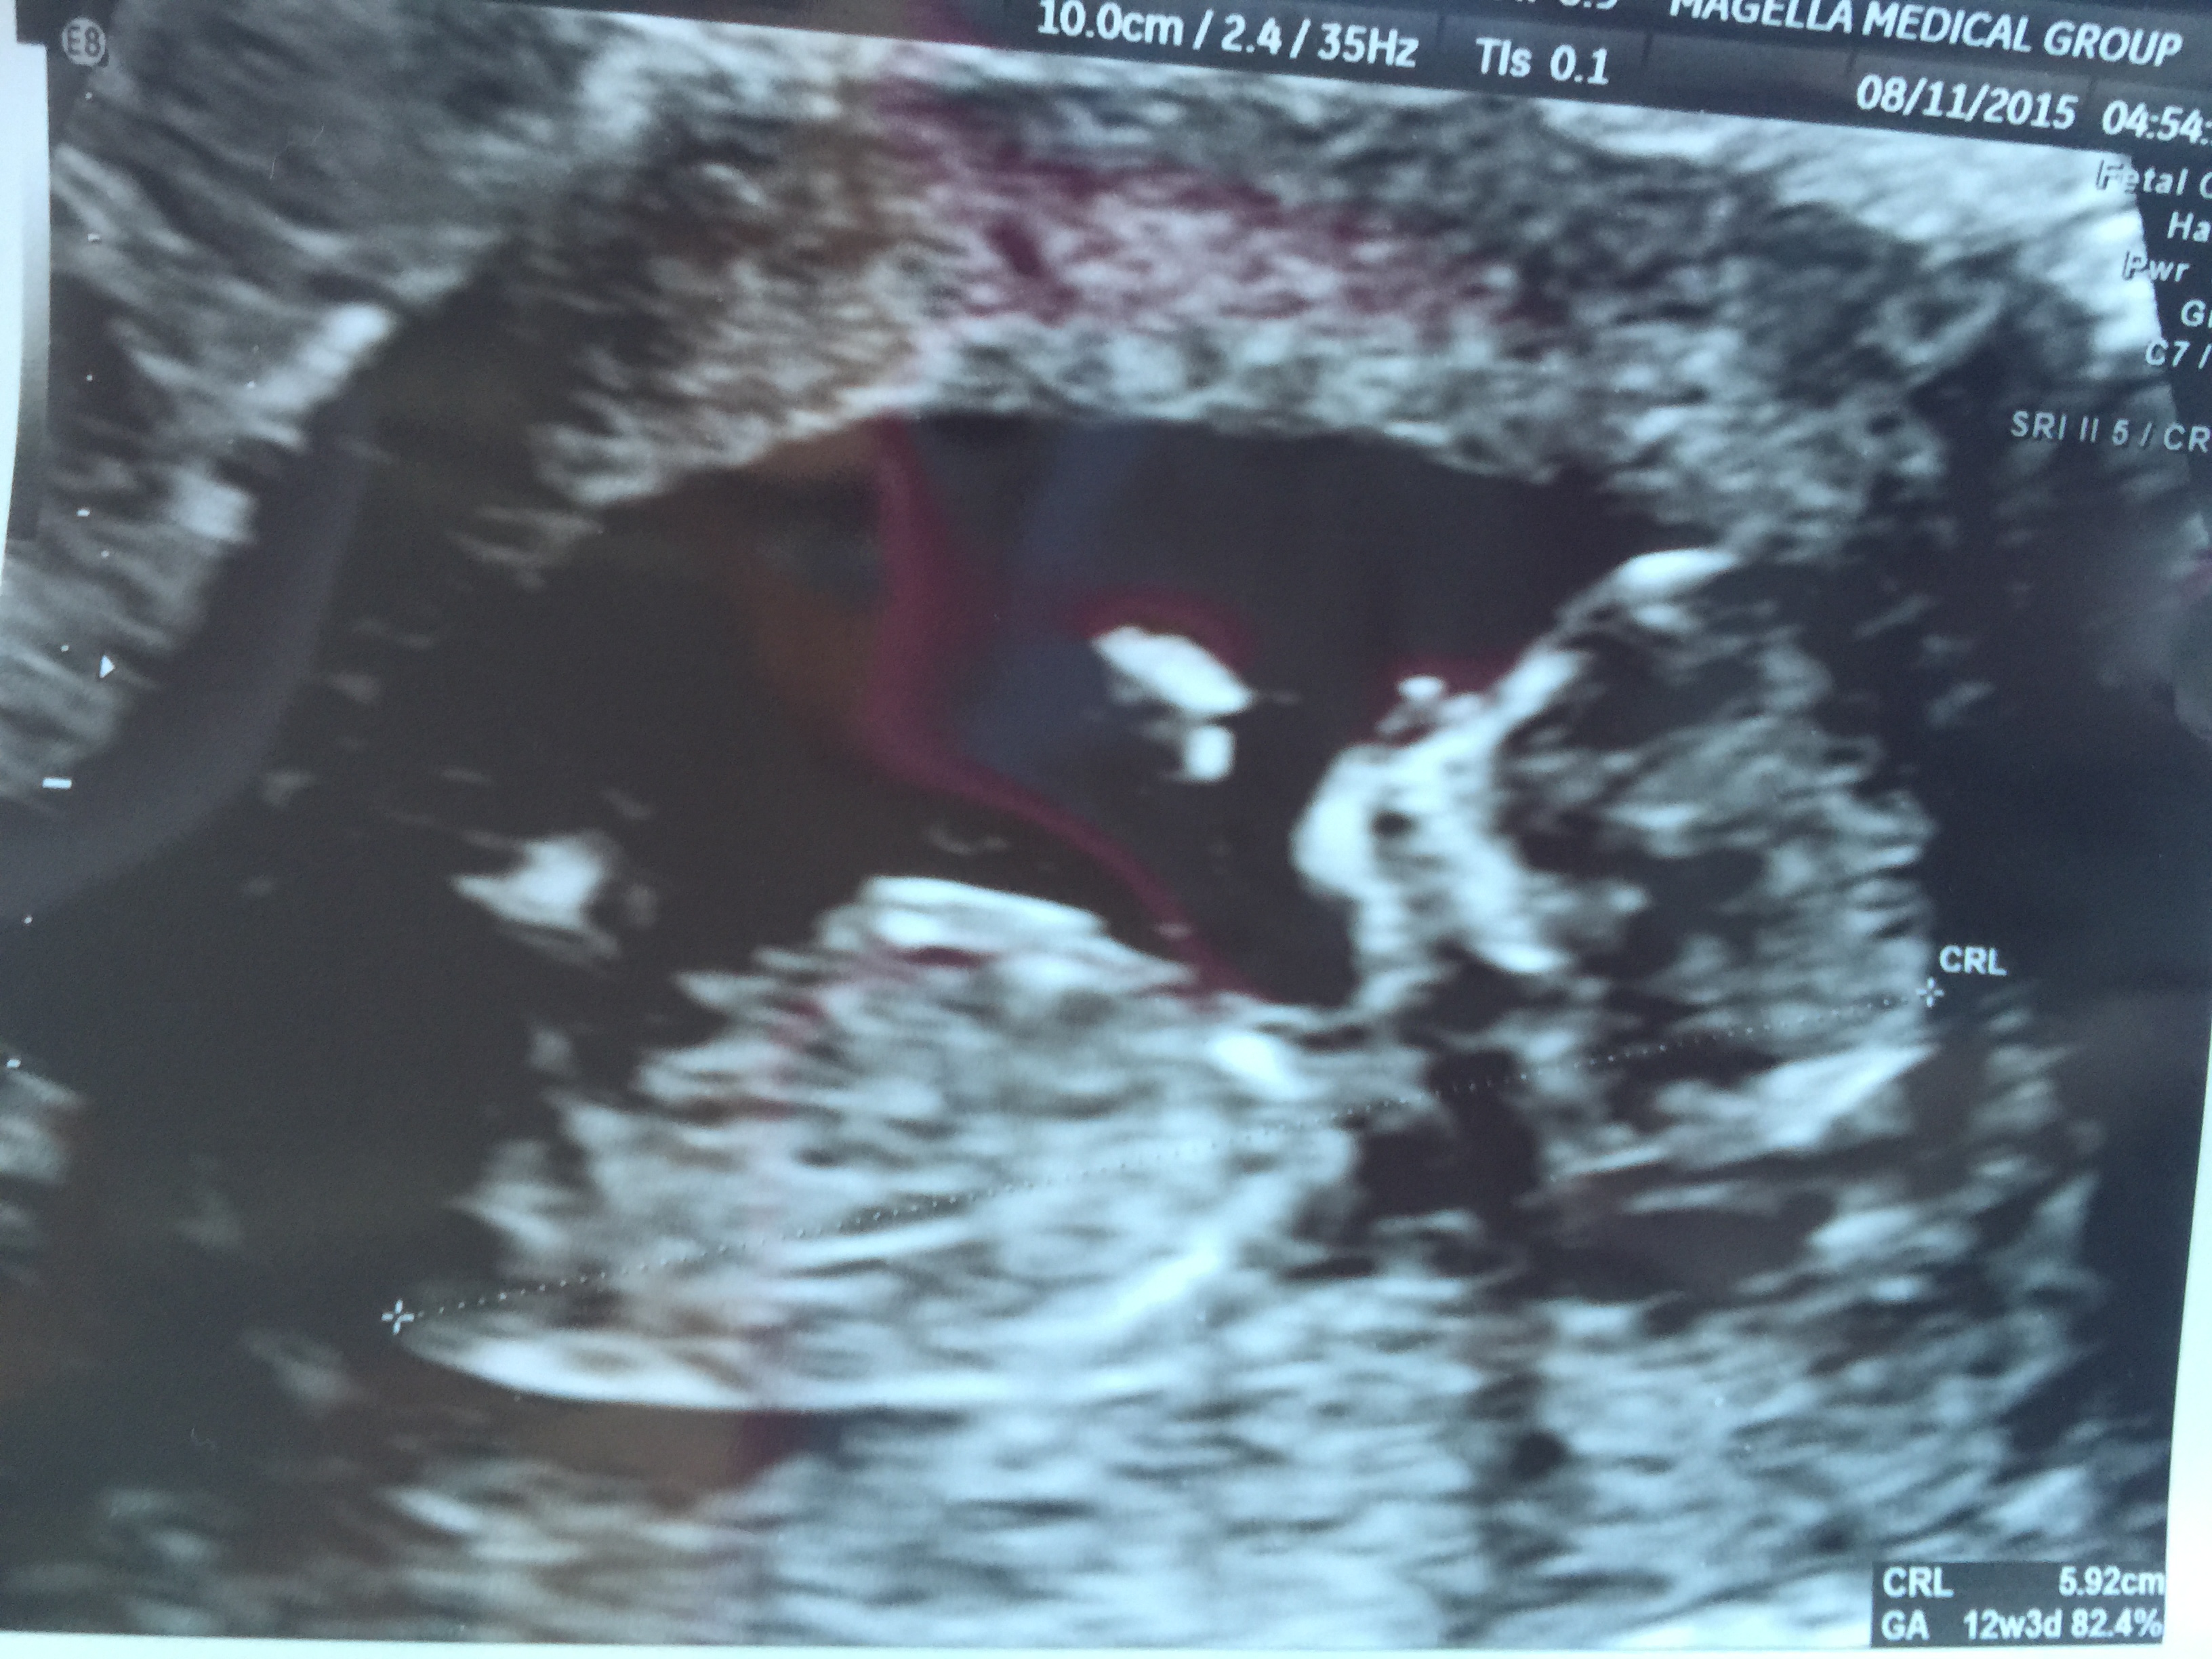

12 week scan. EDD is 2/20 so I'm measuring a little further along at 12wk 5d. HR was 177 and baby was moving and dancing around in there like crazy! So neat to see.